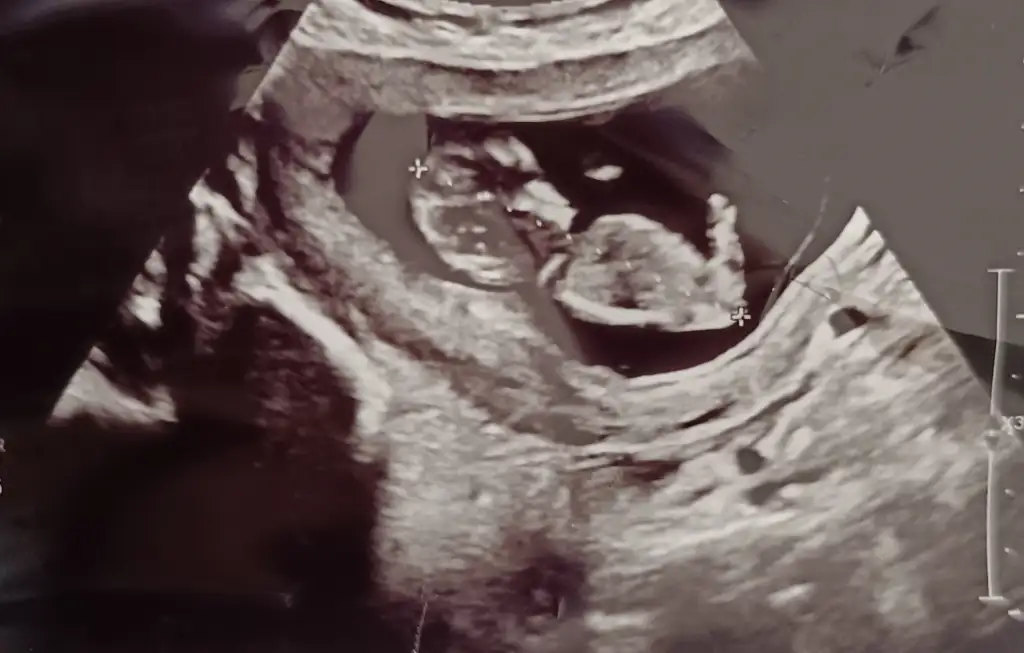

Bana da yorum yapar mısınız ? Arada gibi sanki erkeğin 1. Fotosuna da benziyor kızın 3.fotosuna da ben anlayamadımİnternetten nub teorisi diye arastır sende tahminde bulunabilirsin :)

Nub nasil oluyorki? Hala anlayamadim. 30 derecelik aciya gore dimi? Ben en son 10+2de ultrason muayenesinde oldum. Bi fark olur mu 2 haftada?Kese şekliyle ilgisi yok bence ama nub doğru